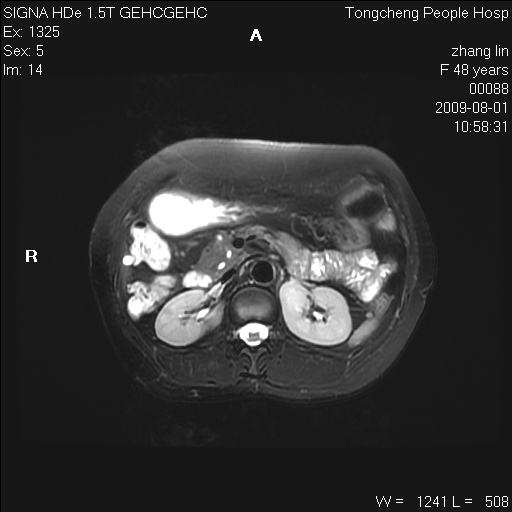

女,48岁。健康体检,彩超发现右肾占位性病变。平素健康。

临床诊断:右肾占位性病变,性质待定(囊肿?肿瘤?)。

上中腹部mr平扫+增强扫描,图像如下:

右肾上极见一类圆形病灶,t1wi呈等信号t2wi呈等高混杂信号,三期增强无强化,边界清---考虑囊肿出血。

同反相位均表现为等信号,病变无强化,考虑含蛋白的囊肿可能,弥散加权相或许有些帮助,

慢性胆囊炎